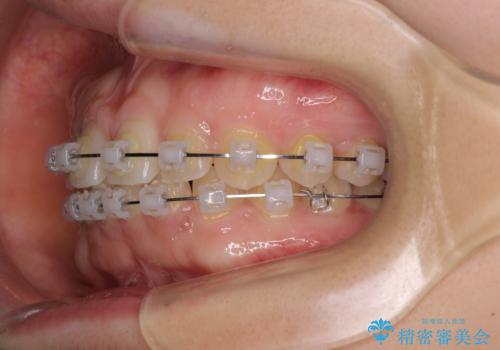

- クリアブラケット

- 前歯の隙間やクロスバイトを気にして来院された患者様です。

結婚式の予定があり、可能であれば結婚式までに治療を終えたいとのことで、短期間で治療をおける可能性の高いワイヤー装置にて矯正治療を行うこととしました。

ギリギリとなりましたが、結婚式直前にワイヤー装置を外すことができました。

ワイヤー装置除去後に細かい部分を短期間のマウスピース矯正にて仕上げました。